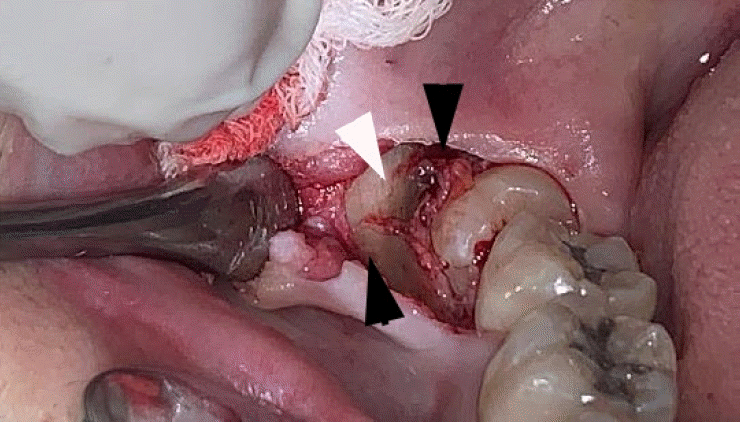

Figure 3.

Alternating bands of blue-gray and yellow discoloration of the alveolar bone observed during flap reflection for surgical extraction of the right mandibular impacted third molar.